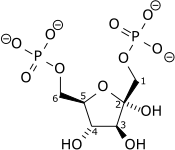

In fructose bisphosphatase deficiency, there is not enough fructose bisphosphatase for gluconeogenesis to occur correctly. Glycolysis (the breakdown of glucose) will still work, as it does not use this enzyme.

There is no problem with the metabolism of glucose or galactose, but fructose and glycerol cannot be used by the liver to maintain blood glucose levels. If fructose or glycerol are given, there will be a buildup of phosphorylated three-carbon sugars. This leads to phosphate depletion within the cells, and also in the blood. Without phosphate, ATP cannot be made, and many cell processes cannot occur.